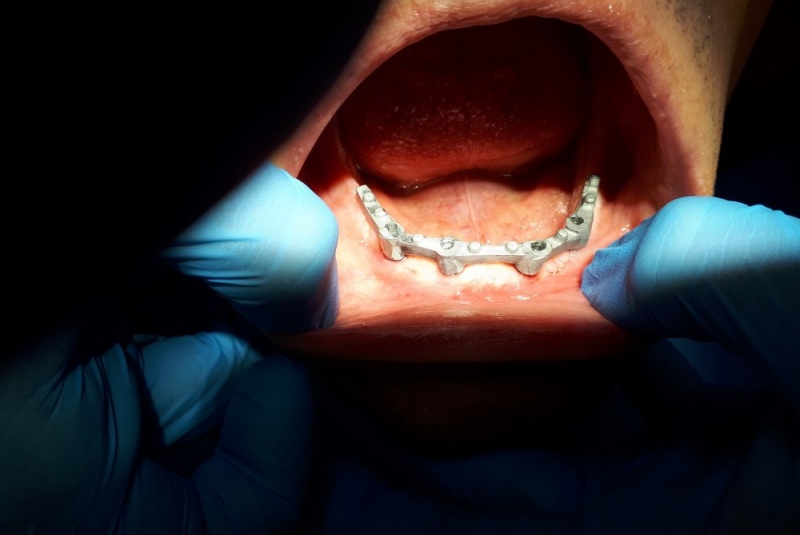

- IMPLANTÁT - je náhrada strateného zuba a používa sa pri strate jedného alebo viacerých zubov, prípadne pri celkovej rekonštrukcii bezzubej čeľuste alebo sánky. Ide o progresívnu metódu, pri ktorej sa zavádza titánová “skrutka” do kosti čeľuste alebo sánky. Implantát tak zastupuje funkciu pôvodného koreňa zuba. V ďalšom kroku sa zhotoví protetická náhrada (korunka, mostík, snímateľná náhrada). Podmienkou pre zavedenie dentálneho implantátu je dostatočná kvalita kosti, ústna dutina bez známok zápalu, či bez zubného kazu a samozrejme dokonalá ústna hygiena.

Totálna implantologická náhrada zubov v dolnej čeľusti